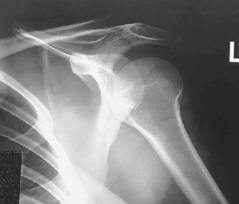

AP external and internal rotation (R)

AP external and internal rotation critique